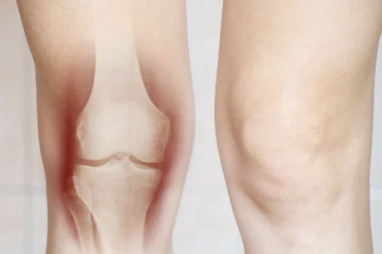

무릎 관절은 우리 몸에서 가장 큰 관절이며, 걷기, 뛰기, 앉기 등 다양한 활동을 수행하는 데 중요한 역할을 합니다. 무릎 관절의 표면을 덮고 있는 연골은 매끄럽고 탄력적이며, 뼈와 뼈가 서로 마찰 없이 부드럽게 움직일 수 있도록 도와줍니다. 하지만 이 연골이 손상되면 무릎 통증, 움직임 제한, 불안정성 등의 문제가 발생할 수 있습니다.

무릎 연골 손상을 의심한다면 전문의 진료를 받아 정확한 진단을 받는 것이 중요합니다. 진단에는 다음과 같은 방법들이 사용됩니다.

- X-ray: 뼈 손상 여부를 확인

- MRI: 연골 상태를 정확하게 진단

- CT: 뼈와 연골 상태를 자세하게 확인